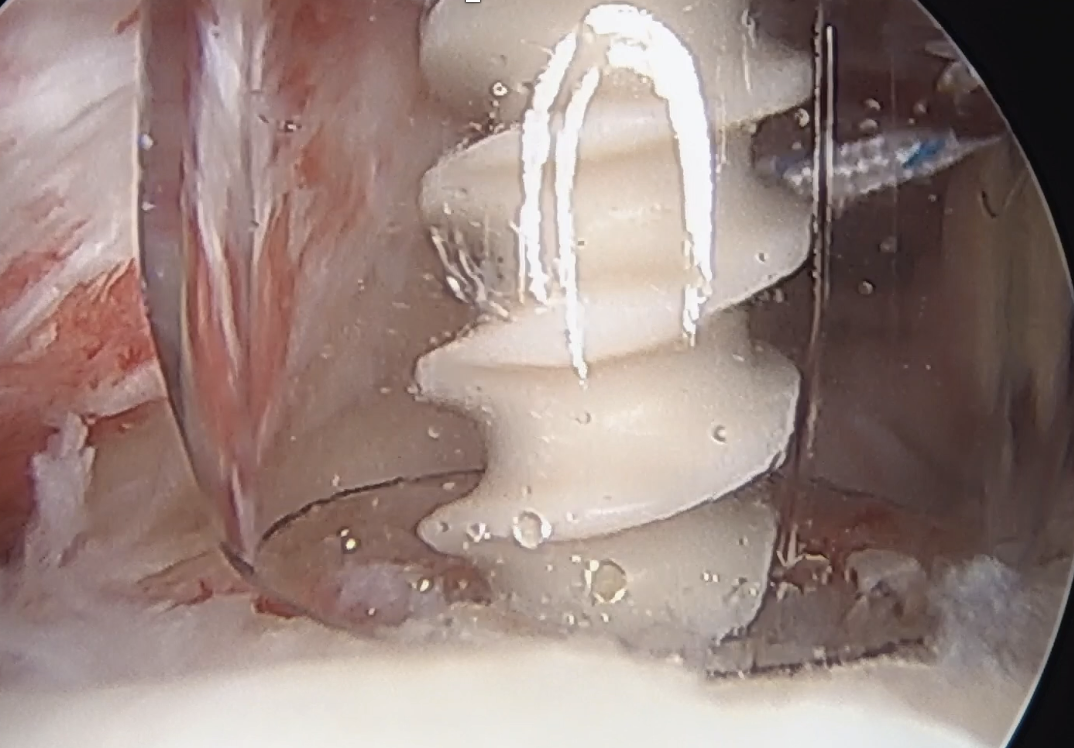

Insert anchor through anterior portal into subscapularis footprint